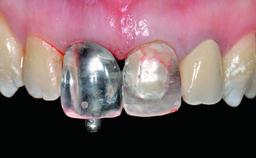

Replacement of an Upper Right Central Incisor with a Root Fracture, Early Placement of an RC Bone Level Implant, Variobase Abutment

Retention Screw-retained Screw-retained

Provisional Implant-Supported Prosthesis Prosthodontic margin > 3 mm apical to mucosal margin Prosthodontic margin > 3 mm apical to mucosal margin